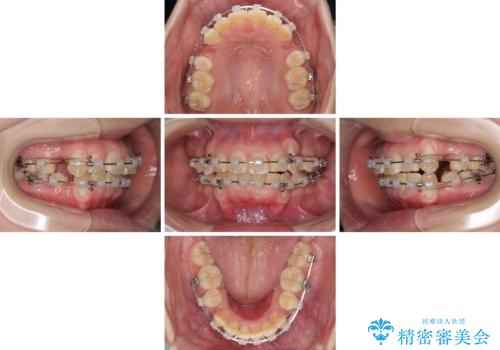

- クリアブラケット

- 2年1ヶ月

前歯部叢生のスペースを獲得するため、上下顎左右小臼歯各1歯を抜歯することとしました。

歯列はきれいに整いますが、歯肉ラインは治療前の歯肉の位置を踏襲します。